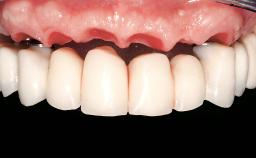

Conventional Loading of Eight Implants in the Maxilla and Final Restoration with a Full-Arch Gold-Ceramic FDP

Prosthesis Type FDP

Defining Characteristics Fully edentulous upper jaw to be rehabilitated with an implant-borne fixed dental prosthesis